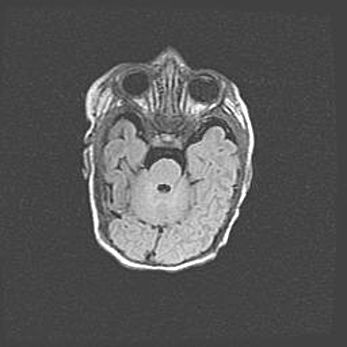

Подострая гематома правой гемисферы мозжечка.

Наружная гидроцефалия.

Возраст: 15 дней

Вес: 3100 г

Пол: женский

Окружность головы: 37 см

Срок гестации: 35-36 недель

При открытой наружной форме гидроцефалии у новорожденных расширяются и переполняются субарахноидные пространства.

Кровоизлияния в мозжечок имеют две клинико-анатомические формы: полушарные гематомы и кровоизлияния в червь.

К появлению этой патологии может привести: повреждения головного мозга, возникающие в результате асфиксии и гипоксии плода при беременности, или травмы во время родов. Редко гематома мозжечка может быть результатом первичной коагулопатии и сосудистой мальформации, диссеминированном внутрисосудистом свертывании, изоиммунной тромбоцитопении.